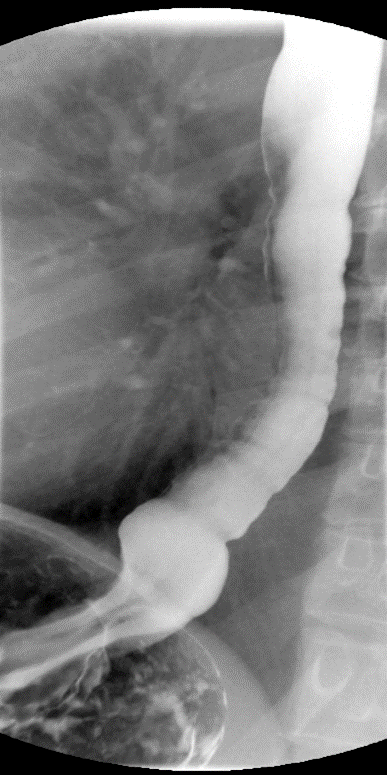

- Continue to slowly instill contrast material until the rectosigmoid has become fully distended with contrast material. Obtain spot images of rectosigmoid colon with the patient in both the right posterior and left posterior obliques

(key image 5).